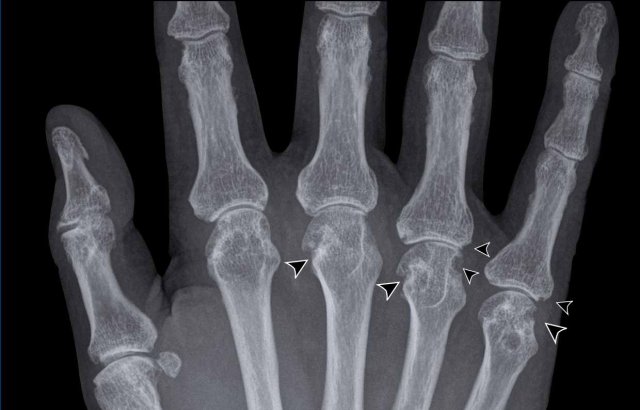

When in doubt, think gout

This is a difficult case.

Small bilateral erosions of the PIP joints on both sides are seen.

The arrowheads show that the erosions are more juxtaarticular in this patient that proved to have gout.

Based on the distribution, rheumatoid arthritis and psoriatic arthritis would have been an option.

However then the erosions would have been more marginally located.

Also, the MCPs are spared, making the diagnosis of rheumatoid arthritis less likely.

Soft tissue swelling

This case is also challenging.

Multipele joint are affected, but there is no typical distribution.

The only thing that these joints have in common is the surrounding hyperdense soft tissue swelling.

This was due to gout tophi.